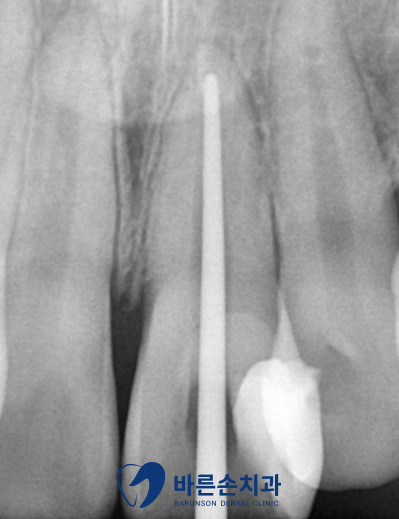

신경을 제거한 후 비어있는 공간을 채워주는 재료(GP콘)를 넣어주고

크라운(보철물)을 씌울 수 있도록 치아를 다듬어줍니다.

그 후 크라운을 제작하기 위해 본을 뜨고

크라운이 제작되는 동안 임시로 사용할 치아까지 만들어드린 후

일주일 정도 지나고 오셔서 크라운까지 붙이면 치료가 끝나게 됩니다.